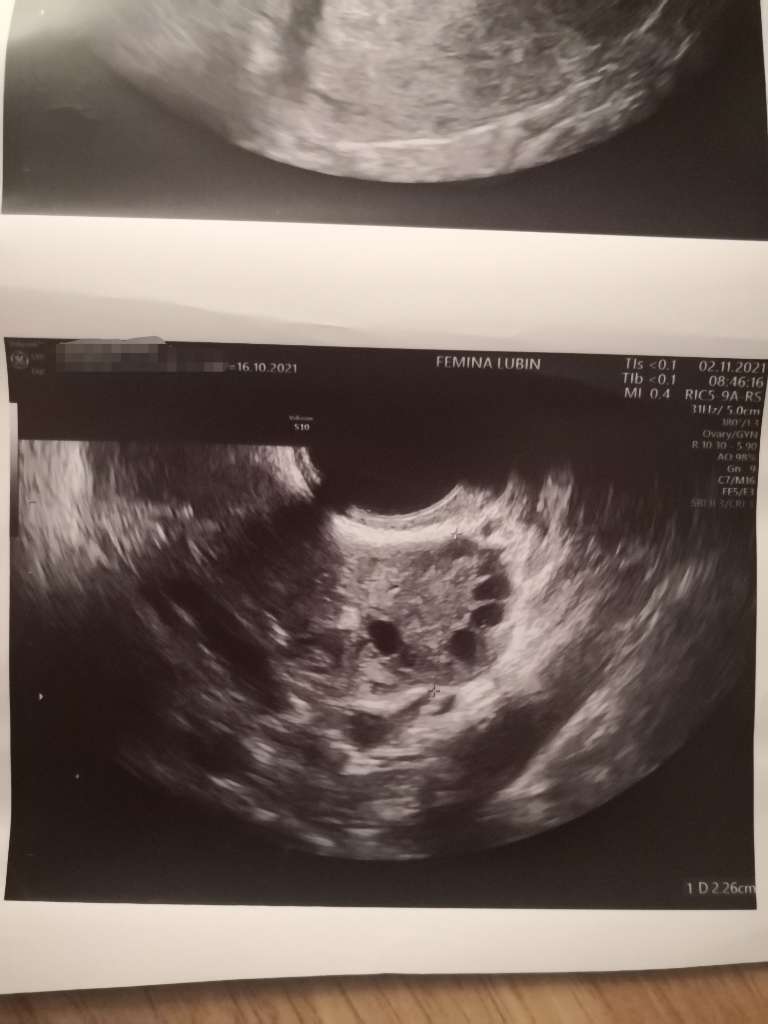

Jezu laski ale każda kobieta ma te czarne kropki na jajnikach (pecherzyki). Jedna ma ich mniej druga więcej i dopóki np nie tworzą koralików dookoła to jest OK. To nie jest tak że bez pcos jest ich 1-2 sztuki. Jest ich mniej ale jednak zazwyczaj występują w liczbie mnogiej.

Wydaje mi się ze te pecherzyki ułożone obwodowo (typowy obraz dla PCO) to taki trochę egzotyczny widok [emoji23] ja mam jeden jajnik wyglądający trochę na PCO (właśnie z uwagi na ułożenie pęcherzyków), ale i badania hormonalne są ok, i owulacje się odbywają, nie mam innych niepokojących objawów wiec po prostu taki se ten jajnik jest. Mniej go lubię, ale jest [emoji16] normalnie te pecherzyki nie są tak ułożone jak korale i może jest ich nieco mniej to i może widok jest mniej szokujący. Mi ostatnio lekarz pokazał bardzo dokładnie ten mój lepszy jajnik tuż po okresie i w sumie to wyglądało to niezachecajaco na moje laickie oko [emoji23]

Gdzieś kiedys czytałam ze najlepiej oglądać pecherzyki antralne na początku cyklu i ze powinno być ich nie mniej niż 5, kilka do kilkunastu. No ale mało kto robi usg podczas okresu [emoji23]

Ja mam takie zdjęcia 🤣 Wiedziałam, że to pęcherzyki, ale nie miałam pojęcia, że ich ułożenie czy ilość mogą wskazywać na pcos 🙆‍♀️